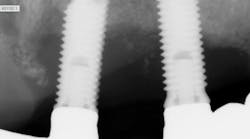

We also take x-rays to check for decay between the teeth or under existing fillings, for cysts and tumors, bone loss from periodontal disease (look for baseline and progression), abscesses, the position of adult teeth before eruption, to treatment plan for braces, and to see missing teeth, possibly for dentures or implants.

It’s not only important to take several x-rays per visit, it’s just as important to take x-rays that are of good diagnostic quality. Cone cuts and overlapping are not diagnostic quality. Sometimes we snap an x-ray and if we can make out an image, we go with it. This is not right!

Did you know an insurance company can deny a procedure if you do not submit good diagnostic quality films? I’ve heard stories about submitting for payment on a cleaning with radiographs, and the insurance company asks to see the x-rays. If the images aren’t diagnostic quality, insurance can deny payment. So, if you take an x-ray that is not good quality, don’t even question, just take it again!